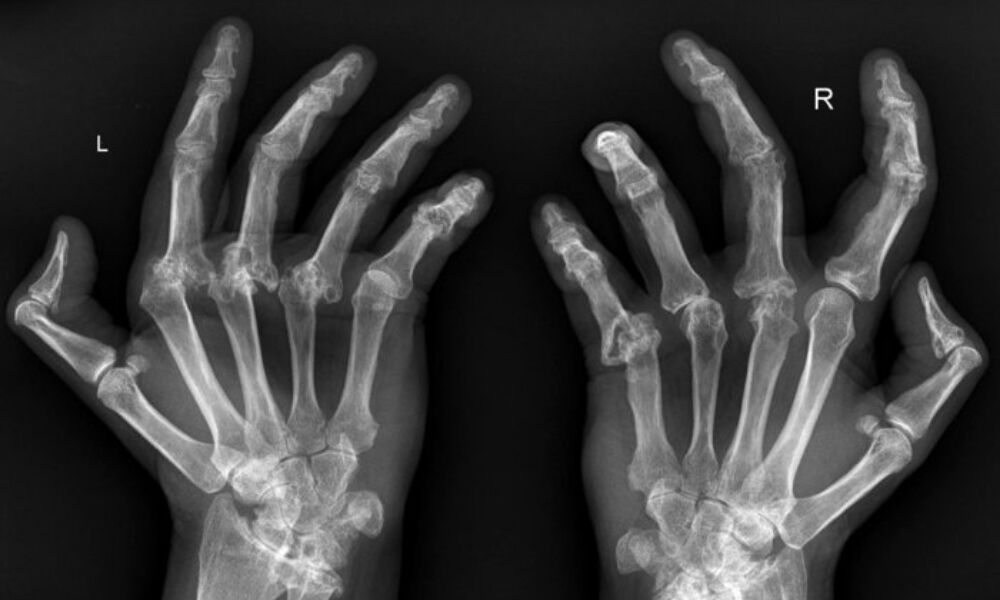

Eklem romatizması, eklemlerde ağrı, şişlik, kızarıklık ve hareket kısıtlılığı gibi belirtilere neden olabilir. Özellikle eller, ayaklar, dizler ve omuzlar gibi eklemler etkilenebilir.

Görüntüleme Tetkikleri: Eklemlerin durumunu daha detaylı incelemek için röntgen, MR veya ultrason gibi görüntüleme tetkikleri yapılabilir.